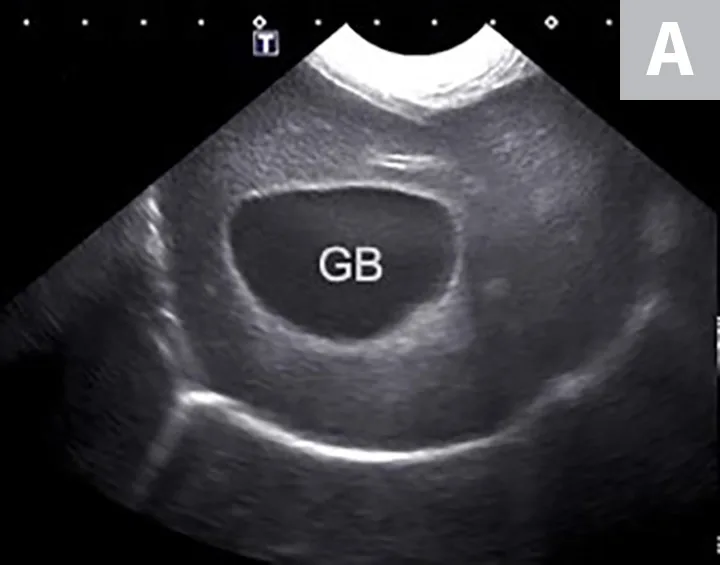

FIGURE 11A

Imaging of a 1-year-old neutered male standard poodle presented with anorexia, lethargy, vomiting, hypoalbuminemia, hypoproteinemia, and cranial abdominal organomegaly. Transverse (A) and sagittal (B) ultrasound of the liver and gallbladder (GB). The liver is enlarged (with increased distance off the stomach from the diaphragm, rounded borders, and extension ventral to the stomach), diffusely hyperechoic, and homogenous. The gallbladder is moderately distended with a normal wall and content. Radiographs demonstrate hepatomegaly and splenomegaly (C). Abdominal ultrasound images revealed splenic enlargement with a mildly mottled architecture and a solitary hypoechoic nodule (D; arrowheads). The pancreas is enlarged and lobulated with multiple hypoechoic tracts and a peripheral capsule (E; between electronic cursors [X’s]). The jejunal lymph nodes are severely enlarged (F; between electronic cursors [X’s]), more than expected for a young dog. The combination of severe hepatosplenomegaly and lymphadenomegaly make systemic disease (eg, infectious, neoplastic) most likely. The appearance of the pancreas is due to pancreatic edema secondary to hypoproteinemia. Acute liver injury was diagnosed, and lymphoma was diagnosed based on hepatic and splenic cytology.